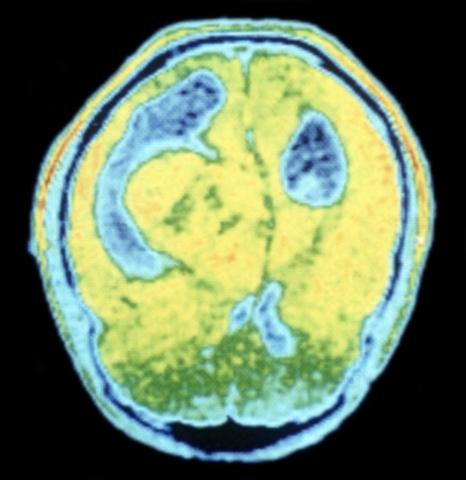

Рис. 2. Цветная ЯМР-томограмма головы (аксиальный срез) при опухоли, распространяющейся в правый боковой желудочек: боковой желудочек растянут и деформирован, продольная борозда смещена (ткань головного мозга и ткань опухоли — желтого цвета, боковые желудочки — синего цвета).